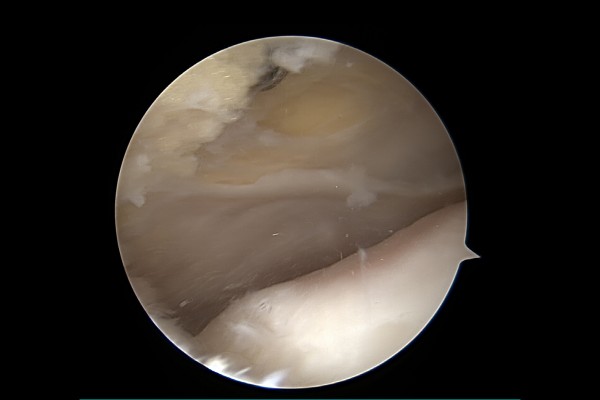

관절내시경 화면으로 보면 슬개골과 대퇴골 사이에 껴있는 너덜너덜한 추벽이 확인됩니다.